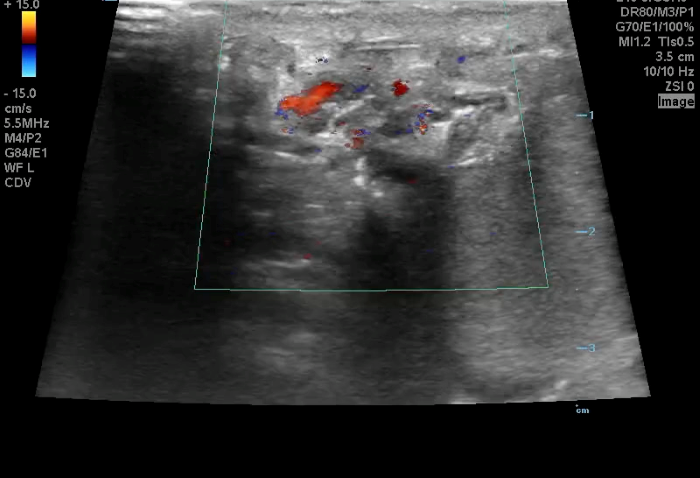

Image 1. Color Doppler of a testicle without blood flow to the body of the testicle concerning for testicular torsion.

In your first image (Image 1), you realize there is no flow with color Doppler. Additionally, you find a torsed cord complex (Image 2), also known as the “corkscrew sign.” You consult Urology who is busy in the operating room with another case. You decide to perform a manual detorsion due to your concern for testicular atrophy and risk of infertility. Using the open book technique, you get relief of pain and return of vertical positioning of the testicle after two rotations. On your repeat testicular POCUS with color Doppler you obtain these images (Images 3 and 4), which demonstrate venous and arterial flow throughout the testicle. The cord is now untwisted and appears linear in orientation.